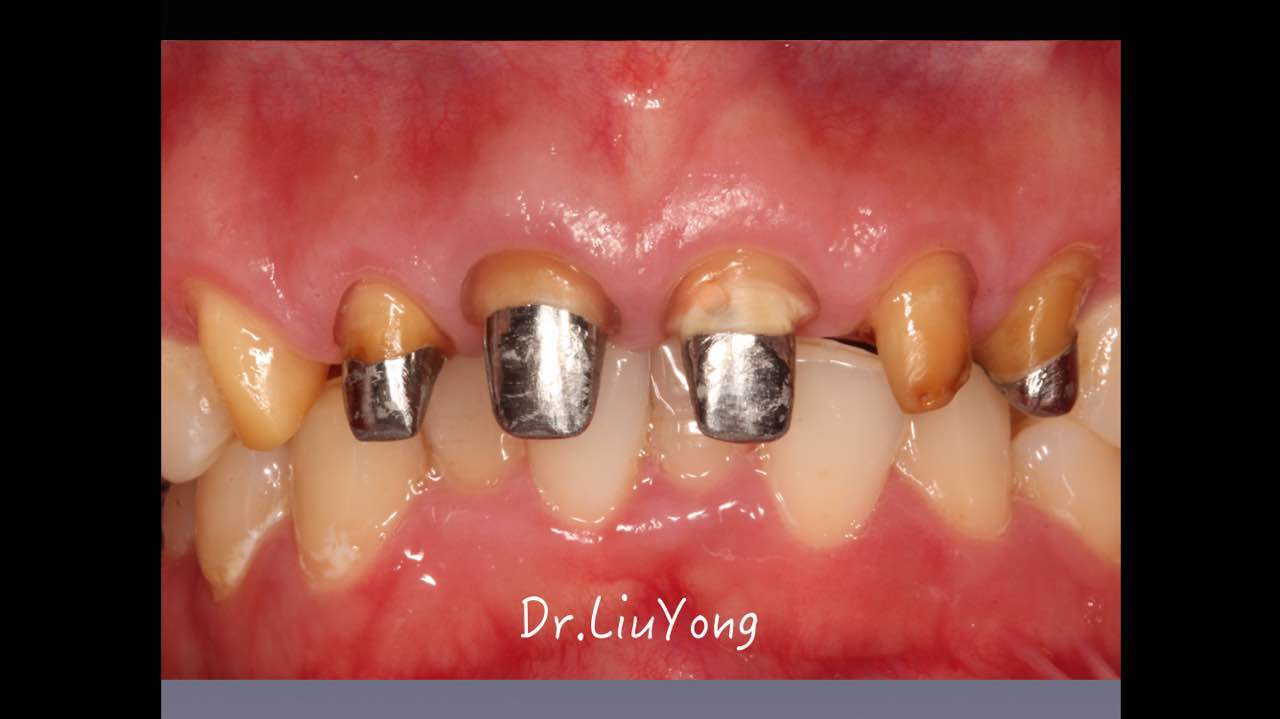

嚴(yán)重破壞生物學(xué)寬度,根尖瘺管,重行根管治療, 第一次冠延長建立唇腭側(cè)及鄰面BW,術(shù)后牙齦扇貝形差, 齦乳頭黑三角,再次行美學(xué)冠延長,建立牙齦扇貝形,手術(shù)免費, 患者因經(jīng)濟原因只能選擇鑄樁及鈷鉻合金烤瓷冠。終于完工